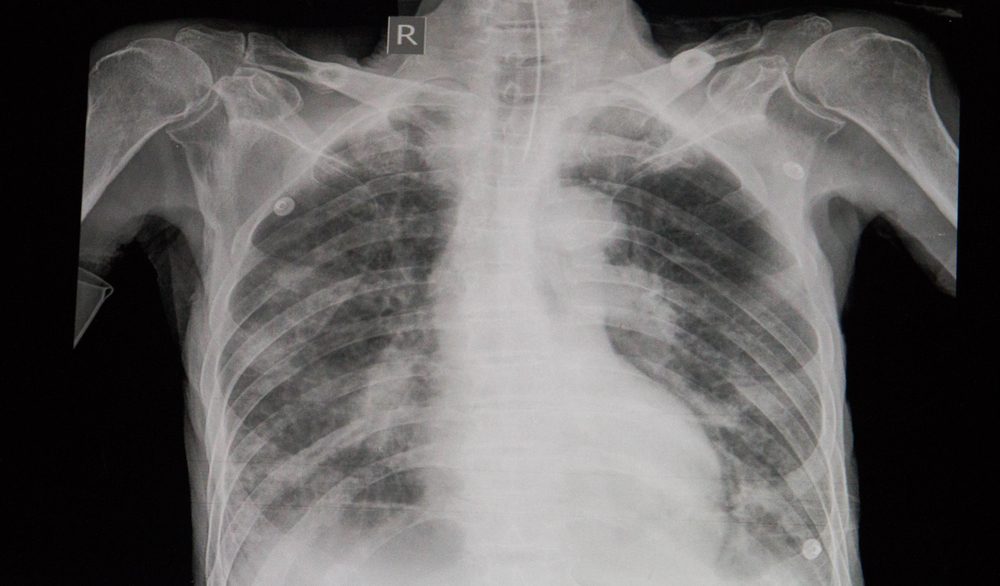

The influenza virus can become deadly when it triggers a sickness like pneumonia—inflammation of the air sacs in the lungs which may then fill with fluid, Dr. Arthur says. The subsequent infection can be deadly. Other serious conditions that can lead to life-threatening infections include inflammation of the heart (myocarditis), brain (encephalitis), and sepsis—the body’s response to infection which triggers inflammation throughout the body and can result in organ failure or death. Keep track of the following signs to know if your flu is becoming more dangerous:

Difficulty breathing

Having a hard time breathing normally—or feeling unusually short of breath—are signs that you’re experiencing flu complications, says Dr. Sonpal. . This is more than a stuffy nose that makes it hard to breathe. An infection like pneumonia makes it a struggle for you to fill your lungs; you’ll be unable to take long deep breaths. Breathing complications are more common in people with asthma or COPD.